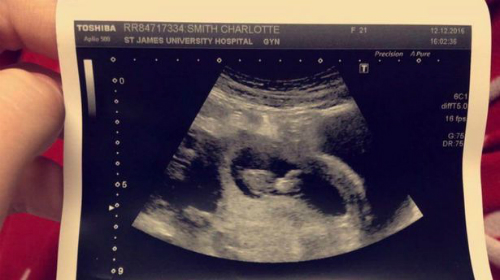

Theo RSVP, Charlotte phát hiện mang thai vào năm 2016. Có con không phải là điều thiếu nữ mới 21 tuổi dự tính song cô vẫn rất hạnh phúc và mong chờ. "Thế nhưng, chỉ vài tuần sau, tôi bắt đầu đổ bệnh", Charlotte chia sẻ hồi tháng 8/2017.

Thoạt tiên, Charlotte bị đau lưng, đuối sức, nôn ọe. Tháng 12/2016, thai được hơn 10 tuần, bà bầu tiến hành xét nghiệm máu và được yêu cầu ở lại bệnh viện qua đêm do kết quả bất thường. 24 giờ trôi qua, bác sĩ thông báo Charlotte mắc bệnh bạch cầu nguyên bào cấp tính, một dạng ung thư máu.

Biết rằng không thể vừa điều trị vừa giữ thai, Charlotte lâm vào tình thế khó khăn. Cô lo cho đứa bé trong bụng nhưng cũng muốn sống. Càng trì hoãn, nguy cơ tử vong càng lớn nên cuối cùng, Charlotte chấp nhận hủy thai kỳ với điều kiện được ngắm con lần cuối. Ngày hôm sau, bác sĩ siêu âm cho Charlotte. Cô không kìm được cảm xúc khi thấy em bé hoàn toàn khỏe mạnh.